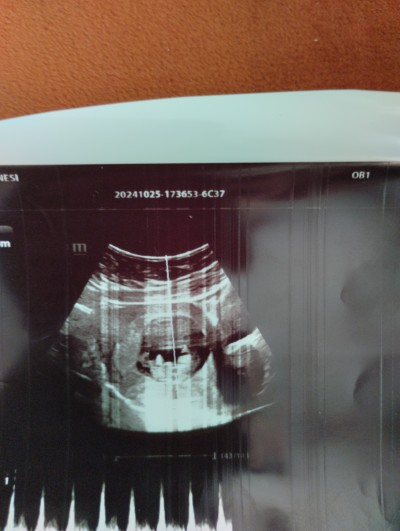

Kız mı yoksa erkek mi? Cinsiyet belirlemede erken dönem ama

Kızlar erken ama bıraz sızce çok merak ediyorum

11+3

Kıza benzettim hayırlısı ile sağ salim kucağına alırsın inşallah

Bende en baştan berı kız hissediyorum ama esım öyle hısetmıyor teşekkr ederım:))

Kaç haftalıksın acaba bende 11 haftalığım 3. Hamileliğim iki oğlum var bunu çok merak ediyoruz

Bende 11+3 bende merak edıyorum o yüzden utrasyın atmıstım